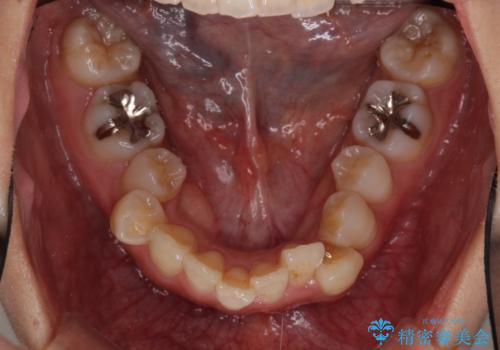

- 上下の歯の前後関係が乱れ、歯に負担がかかるとのことで来院された患者様です。

下顎が右左側に変位しているため、左側奥歯の咬み合わせが上下反対の関係となっていました。

また、上下ともに歯列が狭窄しており、奥歯以外にも反対咬合が認められました。